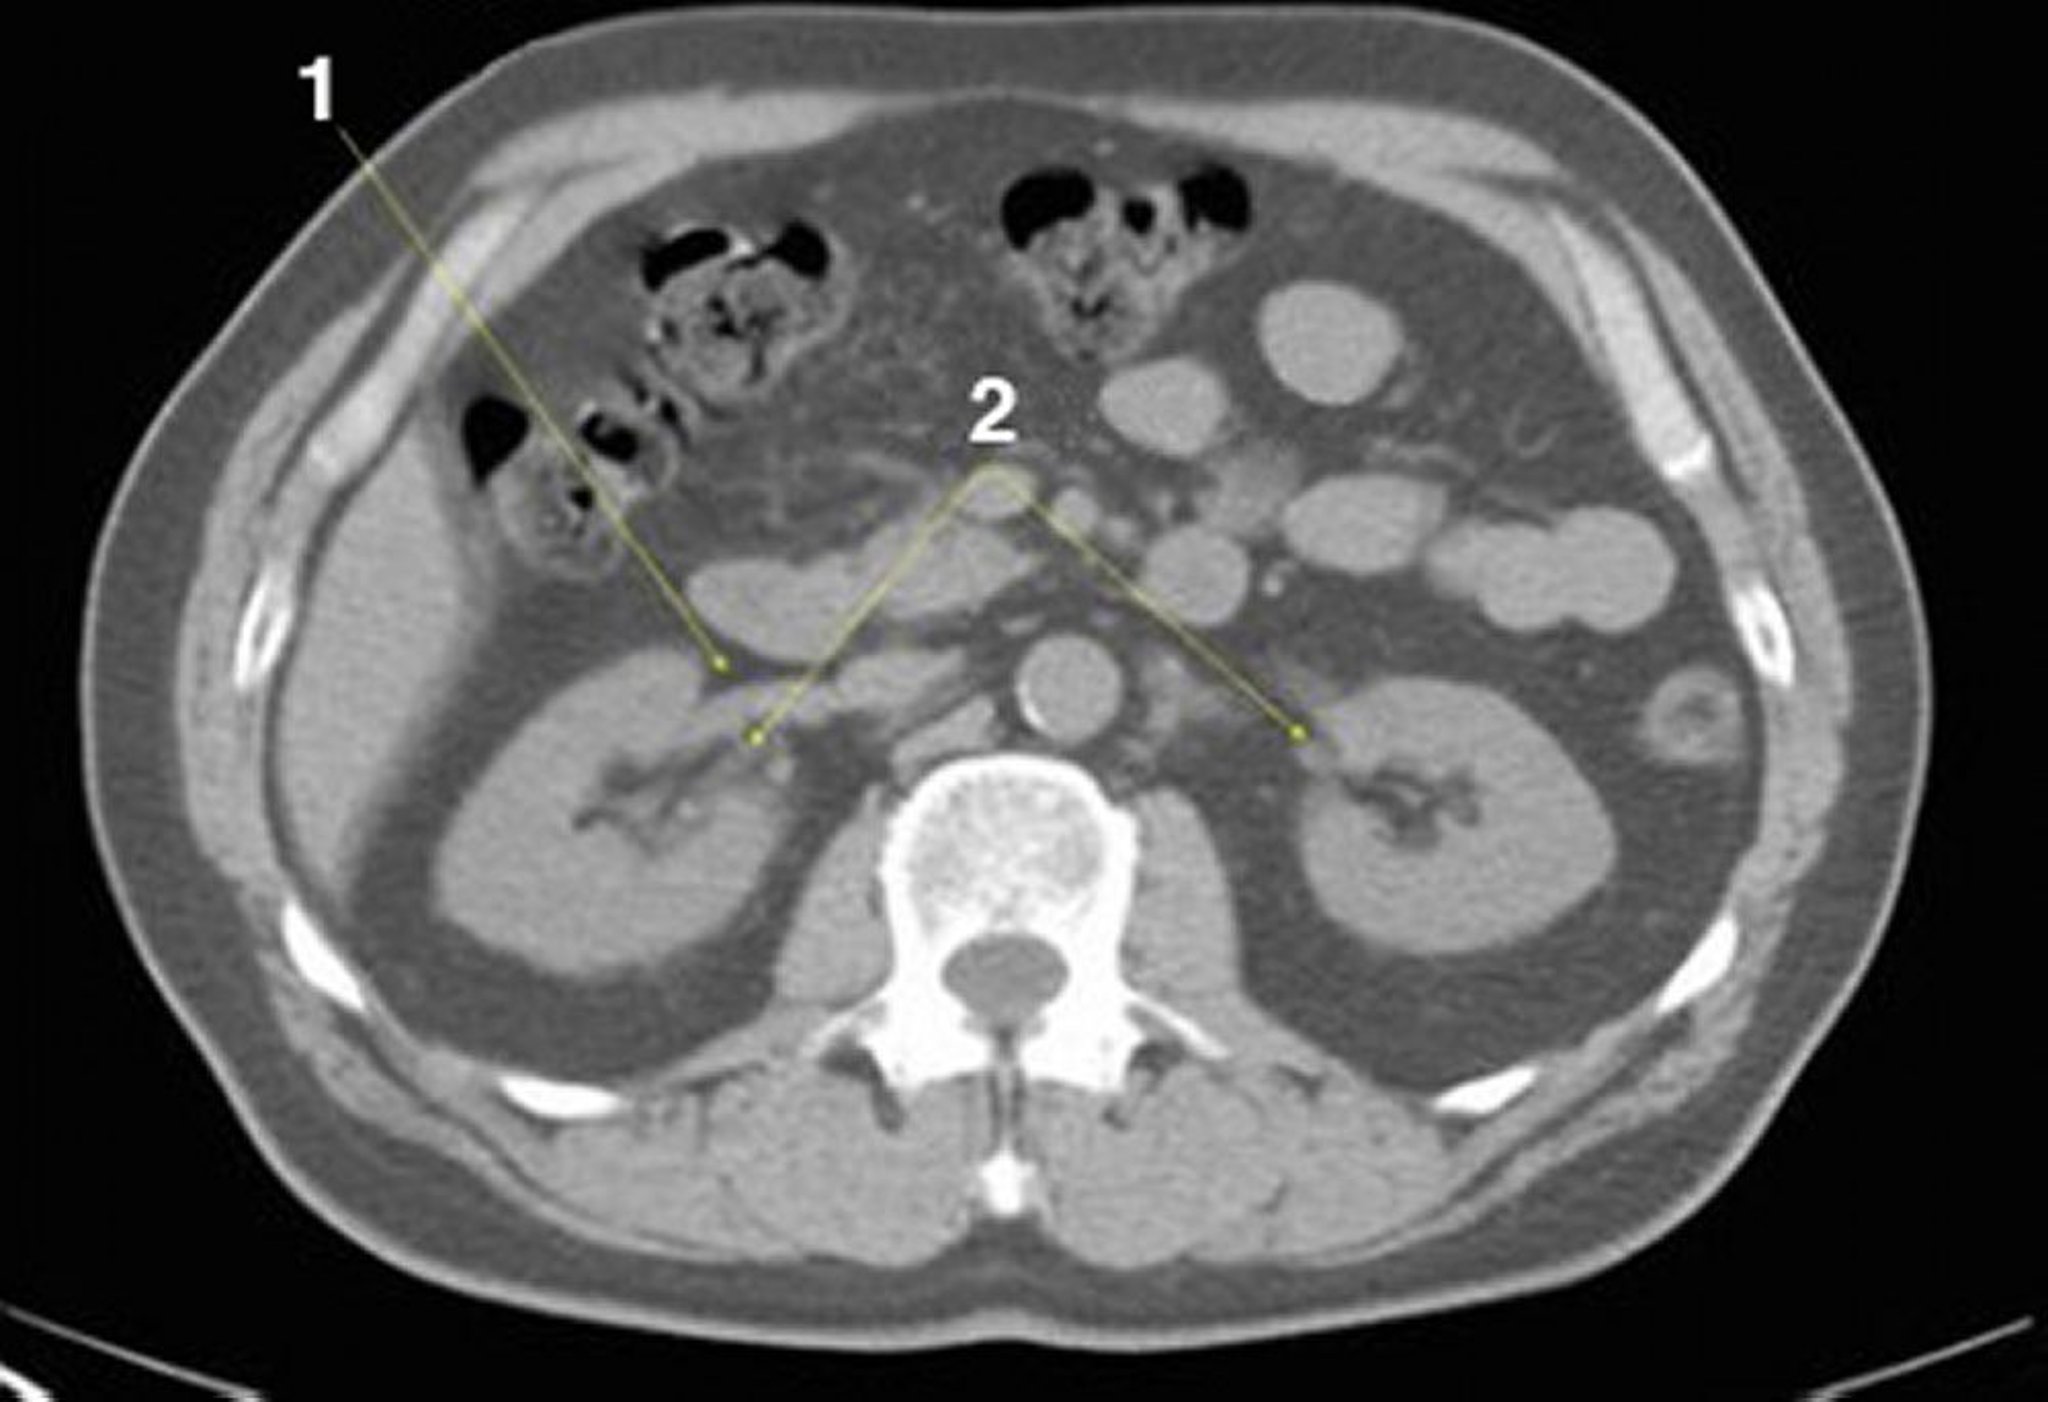

Tomografía computarizada sin contraste de abdomen y pelvis que muestra anatomía normal (imagen 14)

1 = vena renal derecha; 2 = hilios renales.